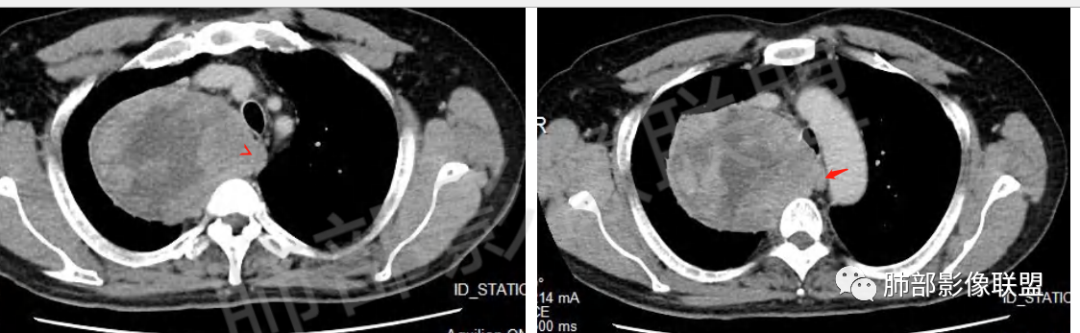

晨读病例,62岁男性,间断咳嗽四个月,影像表现右侧胸腔内见巨大肿块影,边界清晰,其内密度不均,增强扫描病灶呈不均匀性强化,病灶内见坏死及强化的小血管影,考虑恶性病变,肉瘤类病变,纤维肉瘤,滑膜肉瘤,癌肉瘤,恶性纤维组织细胞瘤。

男,62,间断咳嗽4月。胸部CT:右侧胸腔大肿块,向内压气管,向前压上腔Ⅴ,向外挤压右上肺,右上肺体积缩小,瘤肺界面清楚,交界处可见压缩带,胸膜尾可见,平扫密度不均匀,增强可见大片低密度区,AB区?考虑肺外来源,N源性肿瘤(鞘瘤)?SFT?鉴别胸腺肿瘤,肺肉瘤等。

男,69岁,间断咳嗽4个月,右上肺体积缩小,可见巨大软组织占位,胸膜掀起,考虑来源于肺外,平扫密度不均匀,增强扫描明显不均匀强化,内部可见粗大血管及坏死区,周围组织受压移位。局部与食管分界不清,穿刺提示短梭形细胞,来源于间叶组织可能,综合考虑为神经鞘瘤>SFT

边界清楚、光滑,D字征,与肺血管、支气管关系不密切,胸膜被掀起都提示肺外来源

上腔静脉受压前移

提示病灶来源于后方或纵隔外后方,